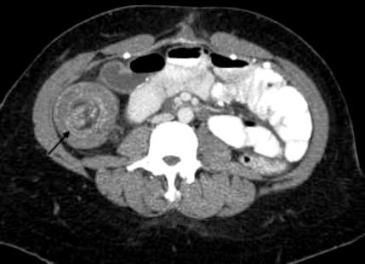

What study would you order to determine the cause of progressively worsening crampy abdominal pain and unintentional weight loss in an older patient with diabetes?

The clinical presentation-crampy abdominal pain after meals, weight loss, and loose stools-is consistent with chronic mesenteric ischemia given this patient's history of diabetes.